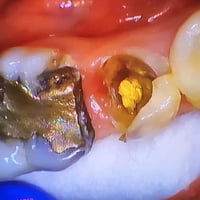

ترميم وبناء سن بحشوة زاركون يابانية تجميلية مع وتد طبيب الاسنان الاختص...

❤️عيادة اسنان للبيع كاملة ❤️ بسعررر ٥ ملييون ونص جير تاوس كلش نظيف اب...